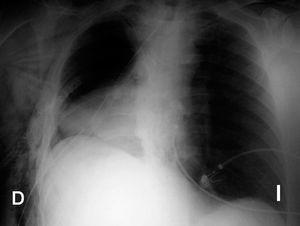

A las 24 horas del postoperatorio y tras extubar al paciente se detecta una imagen radiodensa de forma homogénea en la región inferior de hemitórax derecho (fig. 2) que hace pensar en un nuevo sangrado. En la exploración se aprecia un latido cardíaco débil en hemitórax izquierdo y mucho más intenso en lado derecho, con latido apical visible en sexto espacio intercostal derecho. En la ecocardiografía transtorácica se confirma la sospecha diagnóstica de herniación cardíaca a través de la ventana pericárdica. El paciente fue reintervenido para reintroducir los ventrículos en la cavidad pericárdica y el parche sintético fue sustituido por haber sufrido dehiscencia de suturas, lo que permitió la herniación. El paciente permaneció asintomático en todo momento.

Figura 2